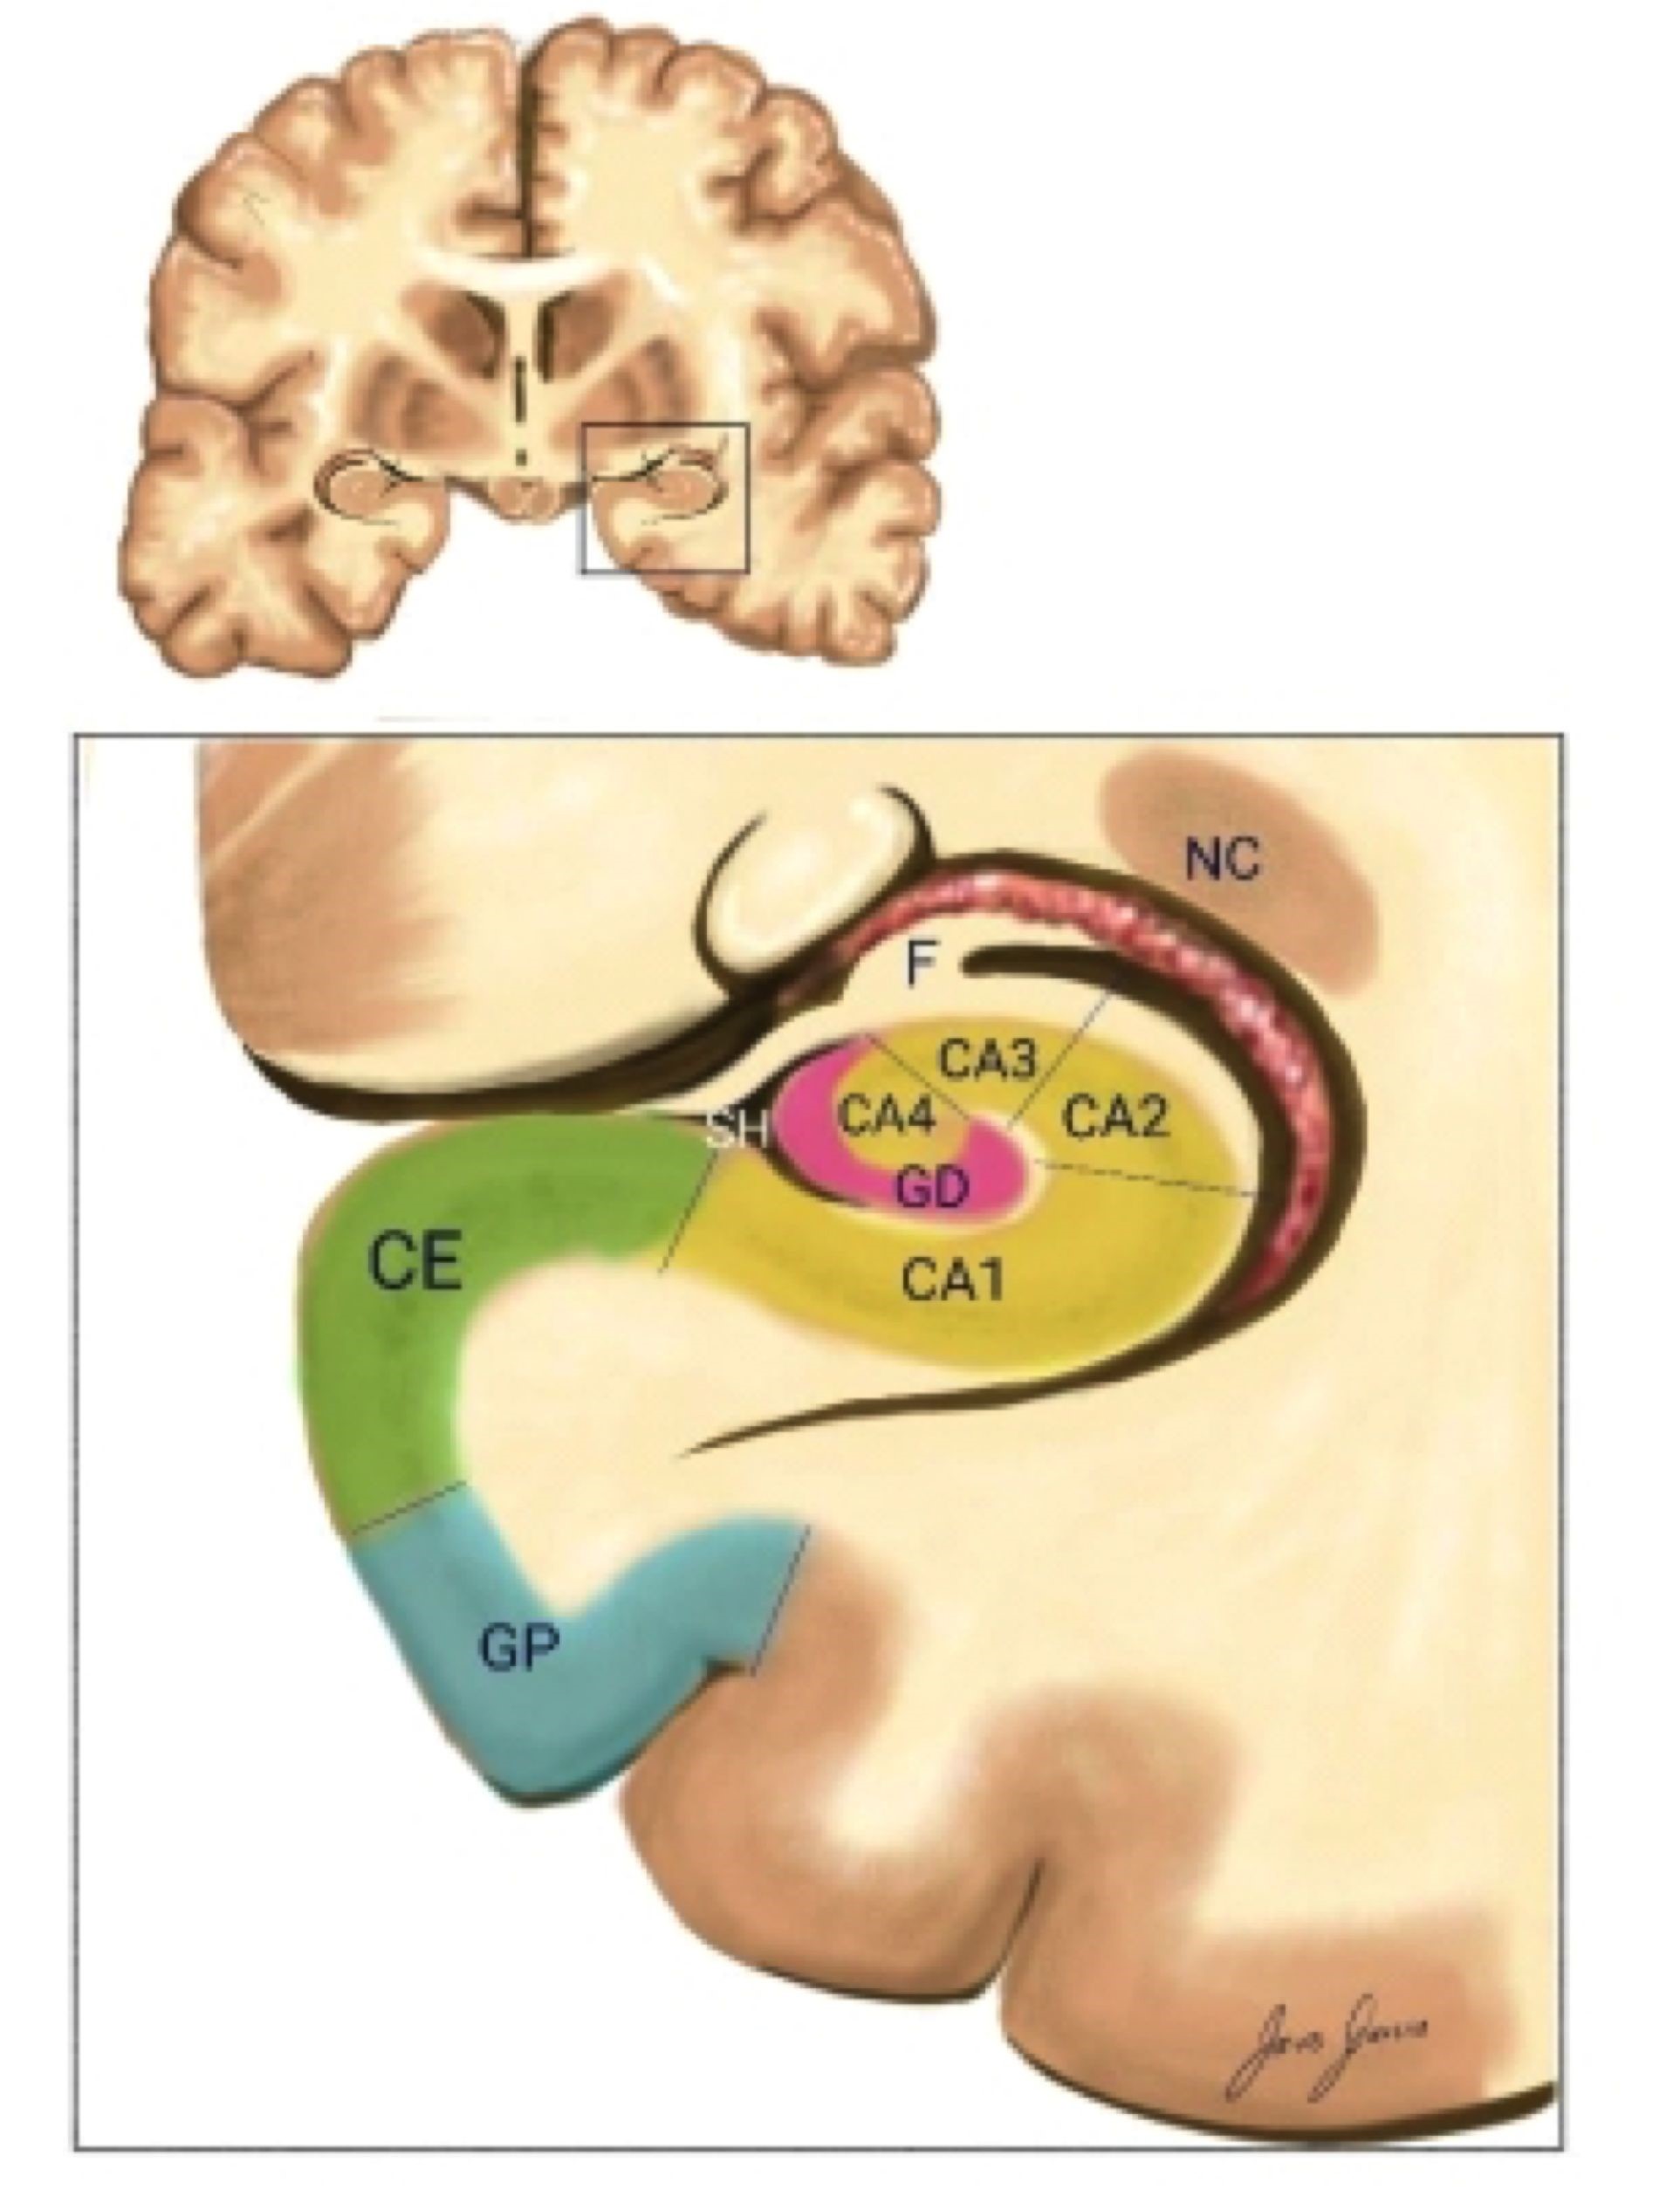

Después del daño hipocámpico inicial se produce una pérdida neuronal con reorganización sináptica en las fibras musgosas, astrogliosis (14) y la formación de circuitos axonales aberrantes que facilitan la presencia de mecanismos de excitotoxicidad y de sinaptogénesis reactiva que contribuyen a la cronicidad de las convulsiones (9). Las alteraciones son más graves en algunas zonas del hipocampo, el cual se encuentra dividido en cuatro regiones CAI - 4 (Figura 1). La esclerosis clásica del hipocampo consiste, principalmente, en una notable pérdida de células en CAI y en la capa polimórfica del giro dentado, seguido de las regiones CA4 y CA3, mientras que las neuronas de CA2 y las células granulares del giro dentado sobreviven (15, 16), existiendo una vulnerabilidad selectiva, no solamente en el cerebro sino dentro del propio hipocampo (17). Esta selectividad lesional se explica por fenómenos ultraestructurales los cuales se basan en que existe mayor densidad de receptores para glutamato en CAI, CA3 e hilus de la fascia dentada.

Es conocida la relación del glutamato con el fenómeno de excitocitosis; el estímulo de sus receptores produce influjo de calcio a las células involucradas con el consecuente efecto deletéreo. Por el contrario, se han encontrado proteínas fijadoras de calcio (calbindina y cromogranina A) en mayor concentración en CA2 y en células granulares de la fascia dentada, estando prácticamente ausentes en CAI y CA3; al actuar como tampones para iones de calcio generan un efecto neuroprotector. Esto se traduce macroscópicamente en atrofia del hipocampo y de las estructuras adyacentes (amígdala, corteza entorrinal y giro parahipocampal (18). ILAE determinó una clasificación semicuantitativa en especímenes como ILAE tipo 1 con pérdida neuronal y gliosis predominantemente en CAI y CA4, la afectación en el sector CA3 Y CA2 es variable; es el tipo más común, aproximadamente entre el 60 % y el 80 % se asocia frecuentemente con historia de lesión, se precipita antes de los 5 años, con inicio temprano de las convulsiones y control posquirúrgico favorable (19,20), ILAE tipo 2 pérdida en CAI y ILAE tipo 3 predominantemente en CA4, y sin esclerosis del hipocampo (21). Existe una clasificación neuropatológica para esclerosis mesial que clasifica la esclerosis hipocampo en tipo 1 a donde CA1 y C A4 son los segmentos más comprometidos, tipo Ib en donde existe pérdida neuronal severa en todos los segmentos del hipocampo y tipo 2 donde existe una pérdida neuronal severa restringido al segmento CAI (22) y el tipo 3 donde existe significativa pérdida neuronal en todos los segmentos a excepción del segmento CAI (23) .